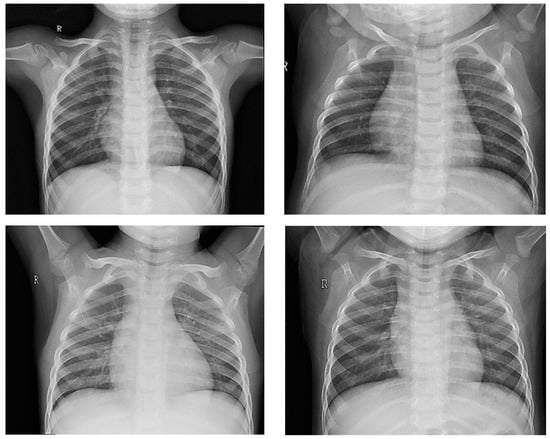

- Ground glass opacities and consolidation;

- Parenchymal abnormalities;

- Interstitial changes;

- Peripheral ground glass opacities;

- Vascular congestion signs;

- Pleural effusion.